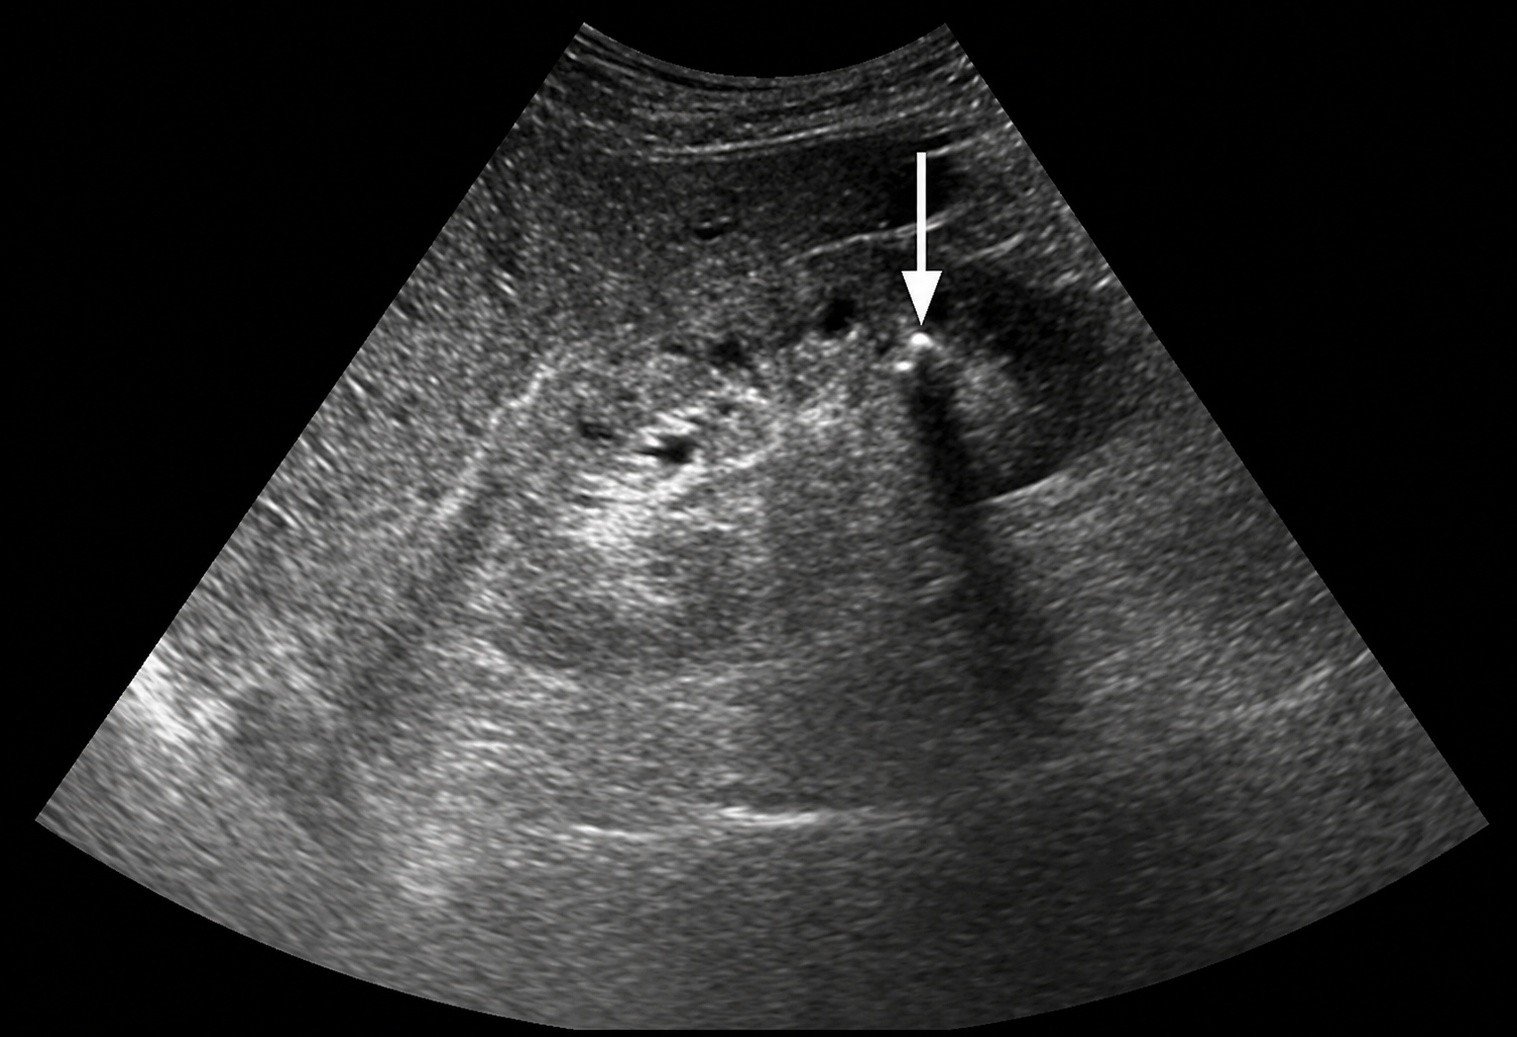

Theo chuyên gia dinh dưỡng Chiu Shih Hsin, bệnh nhân này đã duy trì việc uống 2 viên sủi vitamin C liều cao mỗi ngày trong suốt nửa năm để tăng cường sức đề kháng và làm đẹp da. Tuy nhiên, kết quả xét nghiệm hình ảnh cho thấy thận của cô đã chứa đầy sỏi, giống như một "mỏ đá" thực thụ.